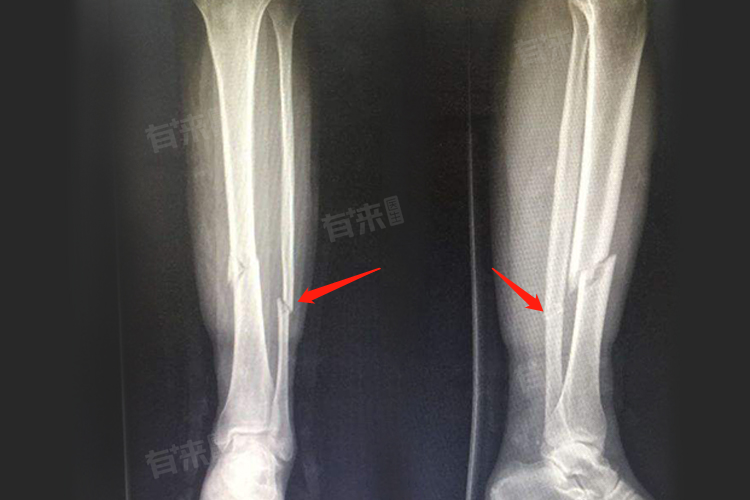

腓骨骨折后正常走路时间受多种因素影响,年轻人代谢旺盛、再生能力强,比老年人早2-4周,无移位单纯骨折6-9周基本能正常走路,粉碎性骨折则需术后3-6个月。

- 如果是无移位的单纯腓骨骨折,一般在石膏或支具固定4-6周后,就可以拆除固定装置。拆除固定后的初期,需要借助拐杖部分负重行走,大概经过2-3周的适应期,也就是骨折后6-9周,基本可以正常走路。

- 粉碎性腓骨骨折的情况较为复杂,愈合时间较长,通常需要手术治疗,采用钢板、螺丝钉等内固定。术后骨折初步愈合一般需要8-12周,这一期间患者可能需要拄拐部分负重行走。正常走路可能要在术后3-6个月,这是由于粉碎性骨折的骨碎片较多,骨折端的血运破坏较严重,需要更长时间来重建骨的连续性和强度。